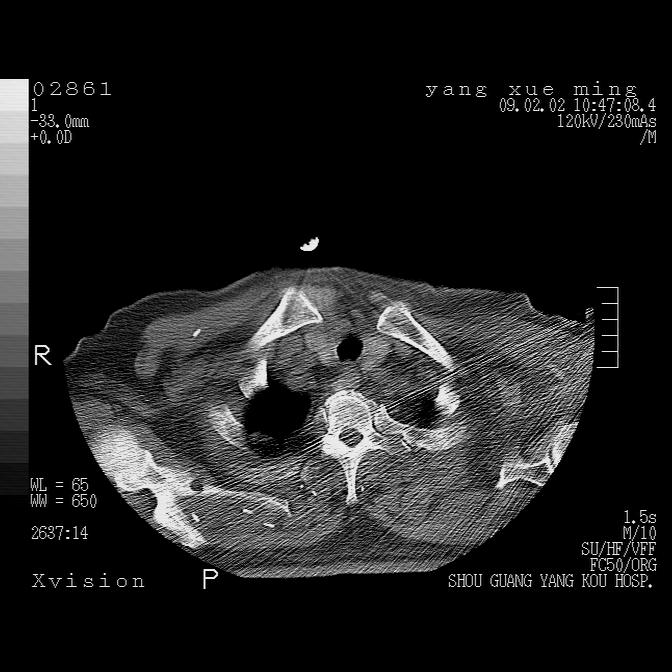

以下是引用lkc8963在2009-2-3 20:11:00的发言:[br]1)右上肺陈旧病灶。2)右下肺团块及团片影,影像表现符合感染。3)左心增大,左冠脉钙化,符合冠心病。4)双侧肺门扩大,以左侧为著,肺动脉干略粗,左上肺局限性气肿,为谨慎起见,需除肿瘤,建议增强。

以下是引用lkc8963在2009-2-3 20:11:00的发言:[br]1)右上肺陈旧病灶.2)右下肺团块及团片影,影像表现符合感染.3)左心增大,左冠脉钙化,符合冠心病.4)双侧肺门扩大以左侧为著,肺动脉干略粗,左上肺局限性气肿,为谨慎起见,需除肿瘤,建议增强.